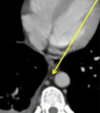

75 ANOS DE IDADE, REFERE DOR TORÁCICA

duplo contorno da borda cardíaca esquerda devido a dilatação da aorta ascendente

ANEURISMA DE AORTA ASCENDENTE